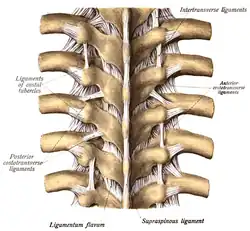

During a laminotomy, the individual lies on his or her stomach with the back facing up towards the physician.[1] An initial incision is made down the middle of the back exposing the vertebrae on which the laminotomy will be performed.[1] In this procedure, the spinous process and the ligaments of the vertebral column are kept intact, but the muscles adjacent to the vertebral column known as the paraspinous muscles (example: spinalis muscle) must be separated from the spinous process and vertebral arch.[1] In a unilateral laminotomy, these muscles are detached only from the side on which the laminotomy is being performed. During a bilateral laminotomy, these muscles must be removed on both sides of the vertebrae.[1] The ligaments connecting the lamina of upper and lower vertebrae, known as Ligamenta flava are often removed or remodeled in this procedure to adjust for the small amount of bone lost.[2] Using either a microscope or an endoscope to have a visual of the procedure, a small surgical drill is used to remove a part of bone from one or both laminae of the vertebrae.[1] Laminotomies can be performed on multiple vertebrae during the same surgery; this is known as a multi-level laminotomy.[1]

Other than static imaging processes, a CT scan can also be used for observing changes in spinal canal features before and after a laminotomy. One of the main signs of lumbar spinal stenosis is the thickening of the ligamentum flavum, causing it to expand towards the spinal canal.[2] When observing the cross sectional area of the spinal canal of a human cadaver, it was found that the area had decreased due to ligamentum flavum thickening. The ligamentum flavum did not appear to alter the dynamic alterations in the dimensions of the spinal cord. Even after the intervertebral disc was removed, the ligamentum flavum did not appear to be a factor in the change in the dimensions of the spinal canal.[6] By understanding the magnitude of the role that ligamentum flavum hypertrophy plays in lumbar sacral stenosis, the necessity of an invasive lumbar spinal procedure can be accurately measured.